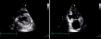

O doente realizou ressonância magnética cardíaca que evidenciou derrame pericárdico de pequeno volume, sem repercussão hemodinâmica, com ganho de intensidade de sinal do espaço pericárdico nas sequências de perfusão, material trombótico parietal nas sequências de realce precoce e tardio e realce tardio pericárdico. Estes achados confirmaram o diagnóstico de pseudoaneurisma dos segmentos médio e basal da parede inferior, parcialmente preenchido por trombo (Figura 2).

Ressonância magnética cardíaca. Sequências SSFP em longo‐eixo de 2 cavidades (A) e curto‐eixo (B) do ventrículo esquerdo, revelando pseudoaneurisma da parede inferior (ponta de seta), derrame pericárdico de pequeno volume; imagens de realce precoce com evidência de trombo (*), preenchendo parcialmente o pseudoaneurisma (C,D); realce tardio transmural envolvendo segmentos basal e médio do septo inferior e segmento médio da parede lateral; no segmento basal inferior, a parede do VE é constituída por trombo (*), cicatriz de enfarte (seta) e pericárdio (ponta de seta), sendo notória a presença de realce tardio sobre os folhetos pericárdicos, confirmando tratar‐se de pseudoaneurisma (E, F).